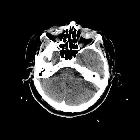

CT

- small and shrunken globe with foci of calcium deposits and ossification in the sclera, cornea, lens, retina, and optic nerve

- distortion of globe components with challenging to separate and identify structures

- fibrotic scarring with irregular globe contour and diffusely increased attenuation